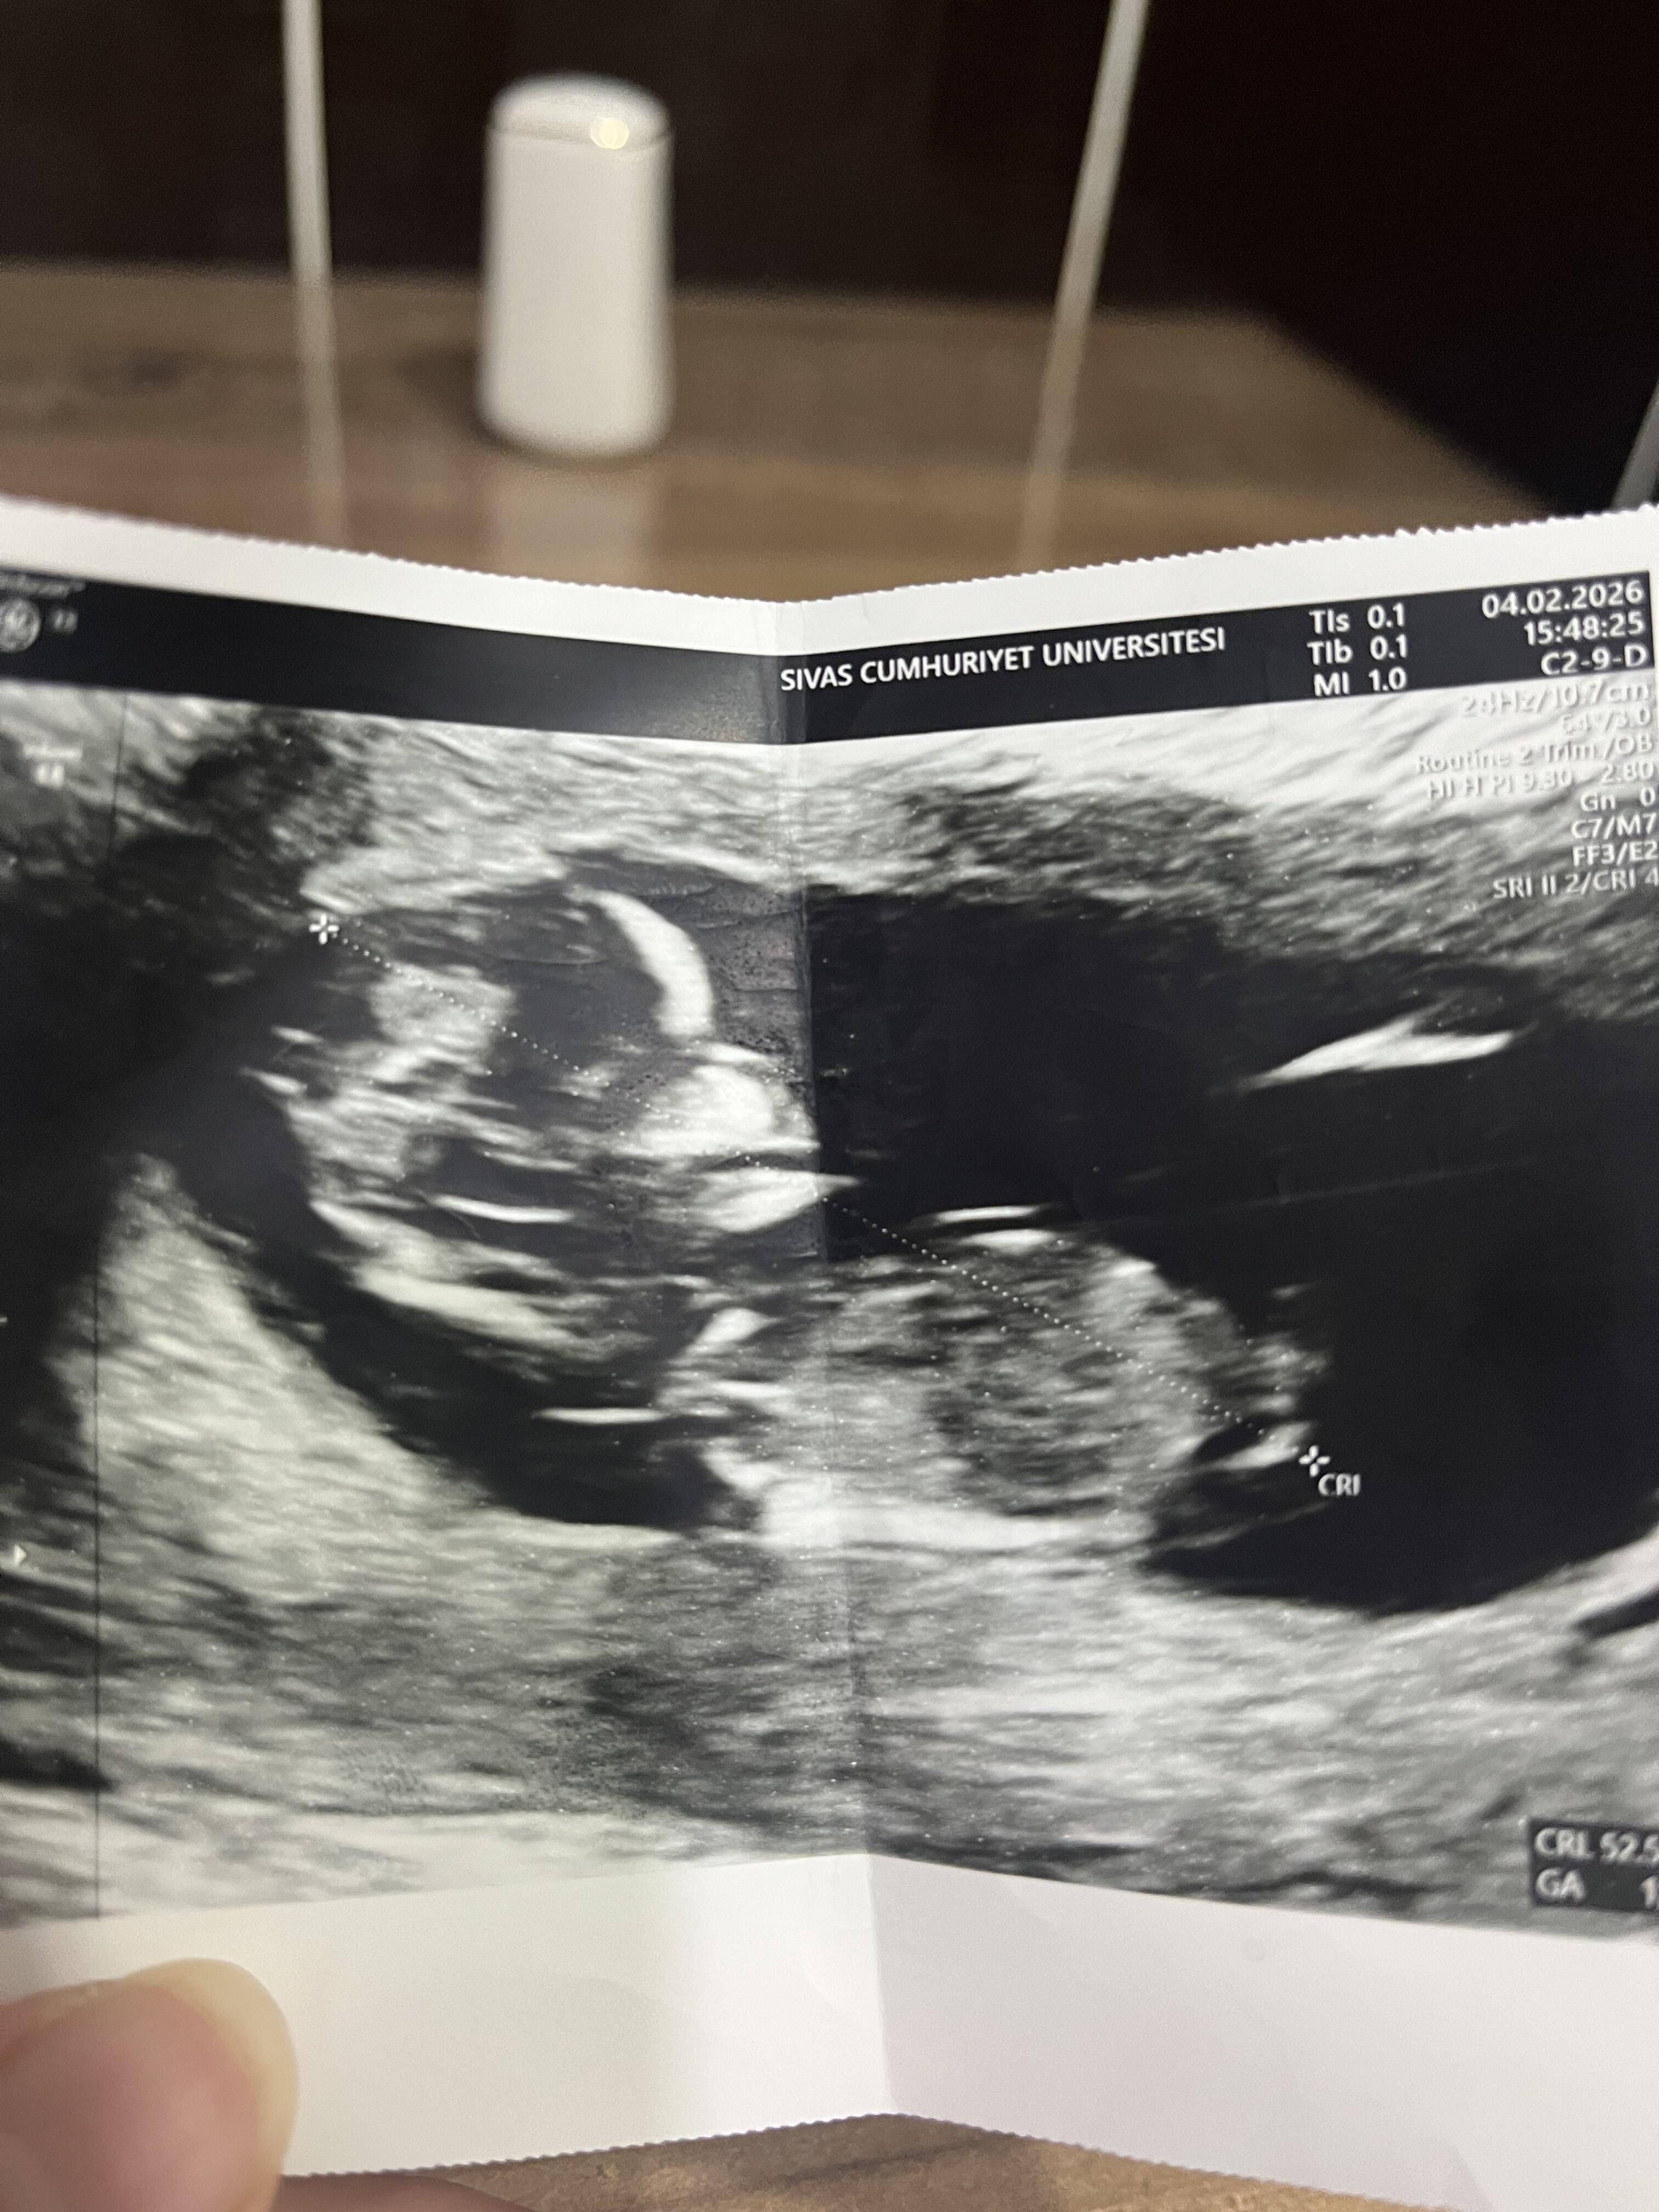

Cinsiyet tahmin

Dr um bi öngörüm var ama demeyeceğim dedi bende erkenden tahmin ettiği için acaba dedim erkek mi?bilen varsa yorumlayabilir mi?

Doktor göremedi bu hafta